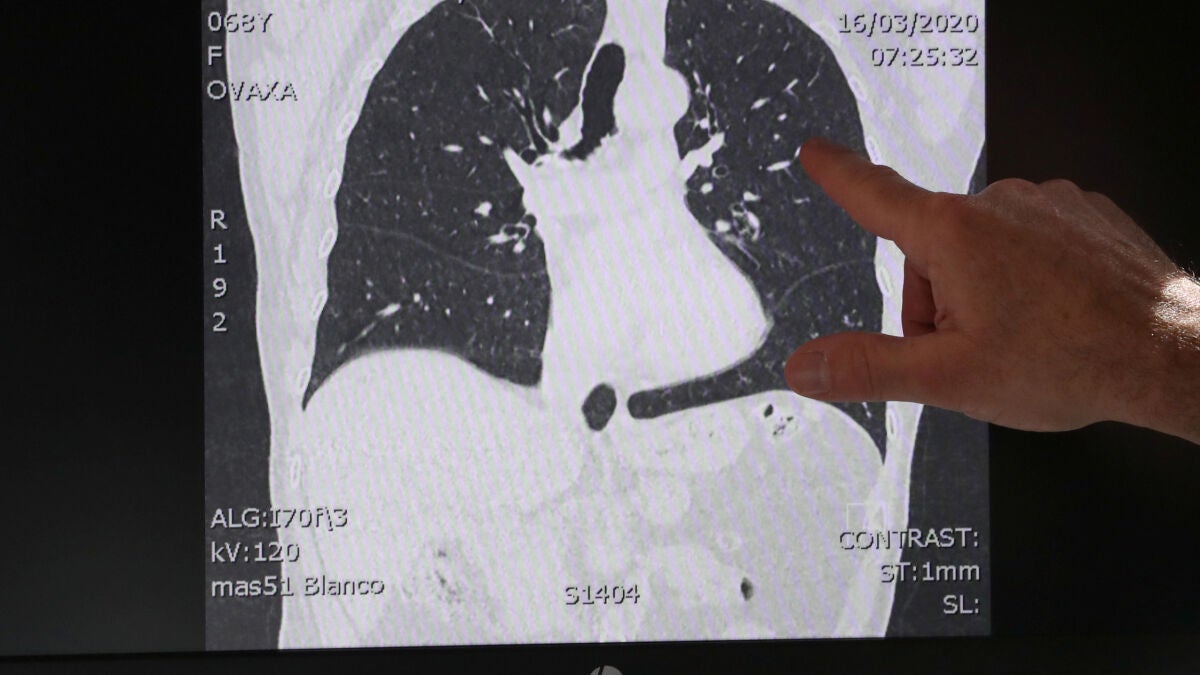

El doctor Ignace Demeyer trabaja en un hospital de Flandes, en Bélgica, y está atendiendo a afectados por el coronavirus. Ha mostrado una serie de imágenes de escáner donde se aprecia la diferencia entre pulmones sanos y pulmones dañados por el COVID-19.

En las imágenes se muestran los efectos de la neumonía que provoca este nuevo coronavirus y que se ha convertido en la peor consecuencia de la infección. Para el 80% de la población la enfermedad cursa con síntomas leves pero hay quien tienen que ser ingresado o, en un menor porcentaje, pasar por una Unidad de Cuidados Intensivos.

El médico asegura que algunas de estas imágenes "dan miedo" y ha decidido mostrar a la opinión pública estos ejemplos para que sean conscientes de que es importante seguir las medidas adoptadas por las autoridades sanitarias.